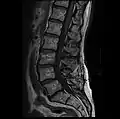

- MRI lumbar spine with degeneration, post-hemilaminectomy L4-5 (sagittal T1 FSE)